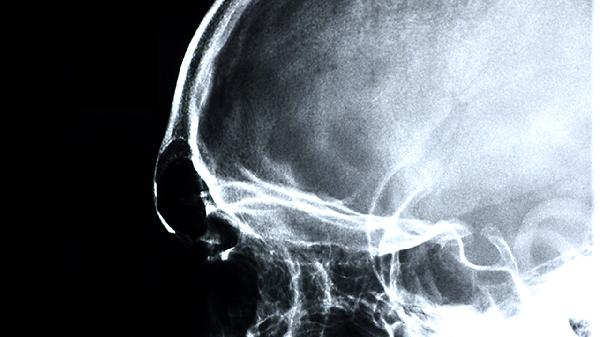

脑得生片具有活血化瘀、通经活络的功效,主要用于瘀血阻络所致的头痛眩晕、中风偏瘫、脑血管后遗症等。主要有改善脑部血液循环、促进神经功能恢复、缓解血管痉挛、减轻脑水肿、辅助治疗缺血性脑血管病等作用。